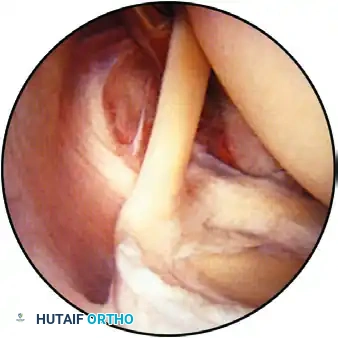

Observation of the superior part of the shoulder joint, demonstrating the biceps tendon inserting into the superior labrum. The humeral head is positioned superior-right, and the glenoid is inferior.

The arthroscope is advanced to evaluate the articular cartilage of the glenoid and the humeral head. The humeral head is dynamically assessed by internally and externally rotating the arm, observing for chondromalacia, osteochondral defects, or traumatic lesions.

On the central glenoid articular surface, a distinct area of thin or absent articular cartilage may be observed. This "bare spot" is a normal anatomical finding and must not be misidentified as an osteochondral defect.